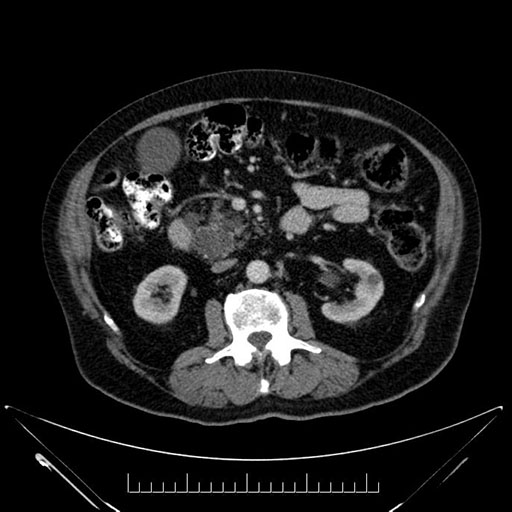

Whipple (pancreaticoduodenectomy) [case 7]

Axial - stented